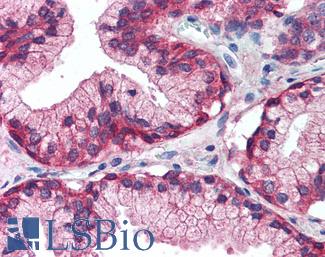

CK7 (KRT7)

Anti-KRT7 / Cytokeratin 7 antibody IHC of human placenta. Immunohistochemistry of formalin-fixed, paraffin-embedded tissue after heat-induced antigen retrieval. Antibody LS-B7164 concentration 10 ug/ml.